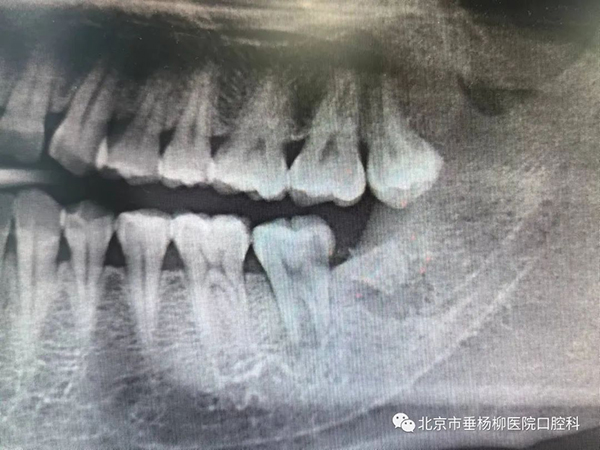

3.智齿大面积龋坏

因为智齿位置最靠后,刷牙时不易清洁,导致智齿更容易患龋。如果是位置正常的智齿,龋坏局限于牙本质中层,可以考虑充填治疗。如果龋坏过深甚至引起牙髓炎,由于智齿根管系统复杂,变异较多,以及患者开口度的限制,根管治疗预后不理想,就建议拔除智齿。

4.邻牙吸收

智齿由于生长空间不足,可能导致邻牙压迫性吸收,最终可能两颗牙都要拔除。